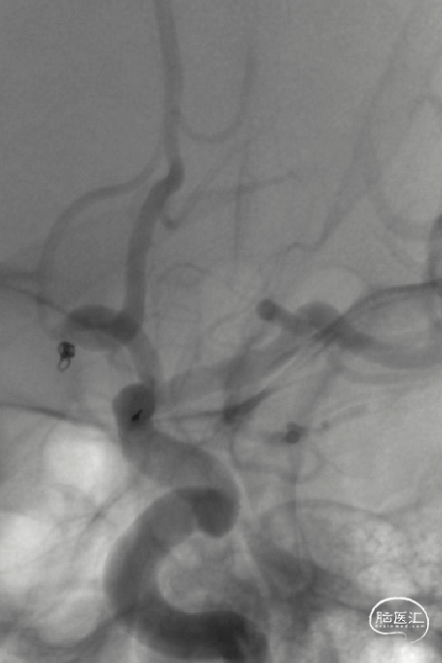

影像信息

前交通微小动脉瘤,伴多个子囊

尺寸:1.6*2.1mm

患者右侧大脑前动脉发育纤细